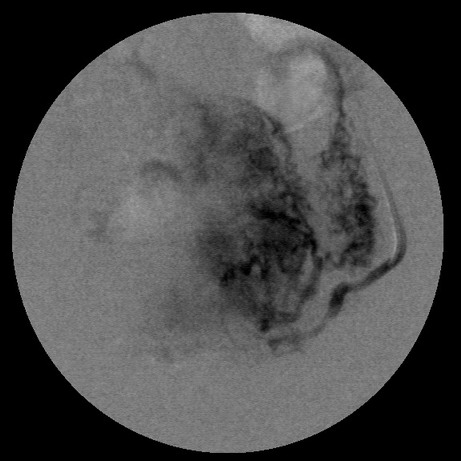

女,35岁,子宫多发肌瘤

请教楼主用的啥栓塞剂!!???栓塞面积是否大了点!?

栓塞剂用的是进口pva,二瓶,几千块呀,栓塞面积应该不大吧,呵呵

左边没有避开卵巢支啊